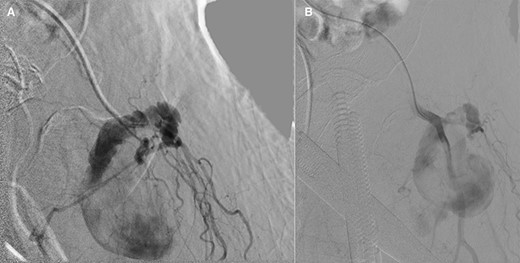

Vascular surgery was consulted and CT angiography demonstrated a large DFA pseudoaneurysm (Fig. 4A and B). Given her advanced years and comorbidities, a minimally invasive approach was recommended. The pseudoaneurysm was successfully embolized using numerous microcoils (Fig. 5). Completion angiography demonstrated complete occlusion of the pseudoaneurysm and patent superficial and DFA (Fig. 5). There were no immediate complications. After discussion with the patient, it was agreed that restarting her apixaban increased risk for her hematoma rebleeding and no anticoagulation was continued for stroke prevention.

Postcoil embolization digitally subtracted angiography via a diagnostic catheter positioned in the left DFA demonstrating adequate embolization of the injured small DFA branch with complete exclusion of the pseudoaneurysm.